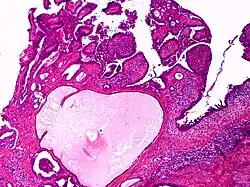

Apocrine gland carcinoma, papillary type

Apocrine gland carcinoma is a cutaneous condition characterized by skin lesions which form in the axilla or anogenital regions.[1]: 670